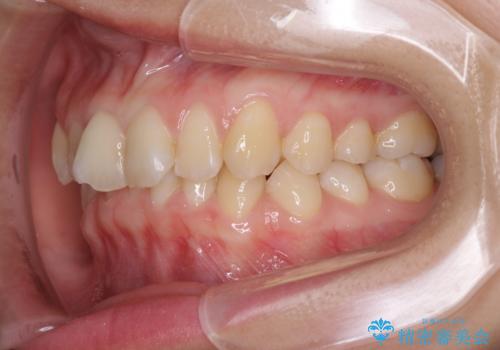

- 口元の深い咬み合わせ(ディープバイト)を気にして来院された患者様です。

インビザラインによる上下歯列の遠心移動(後方移動)により、口元のデコボコとディープバイトを改善することとしました。

下顎左右の犬歯とその後ろにある第一小臼歯、計4歯がシミュレーション通りに動かずディープバイトがなかなか改善されませんでした。

マウスピースの再製作を何度か行いましたがうまくいかないため、部分的にワイヤー矯正を併用することを提案しました。しかし、最も気になっていた前歯のデコボコはきれいに改善されたため、これ以上治療を希望されず、治療を終了することとしました。(今後気になった際には再開する予定です)